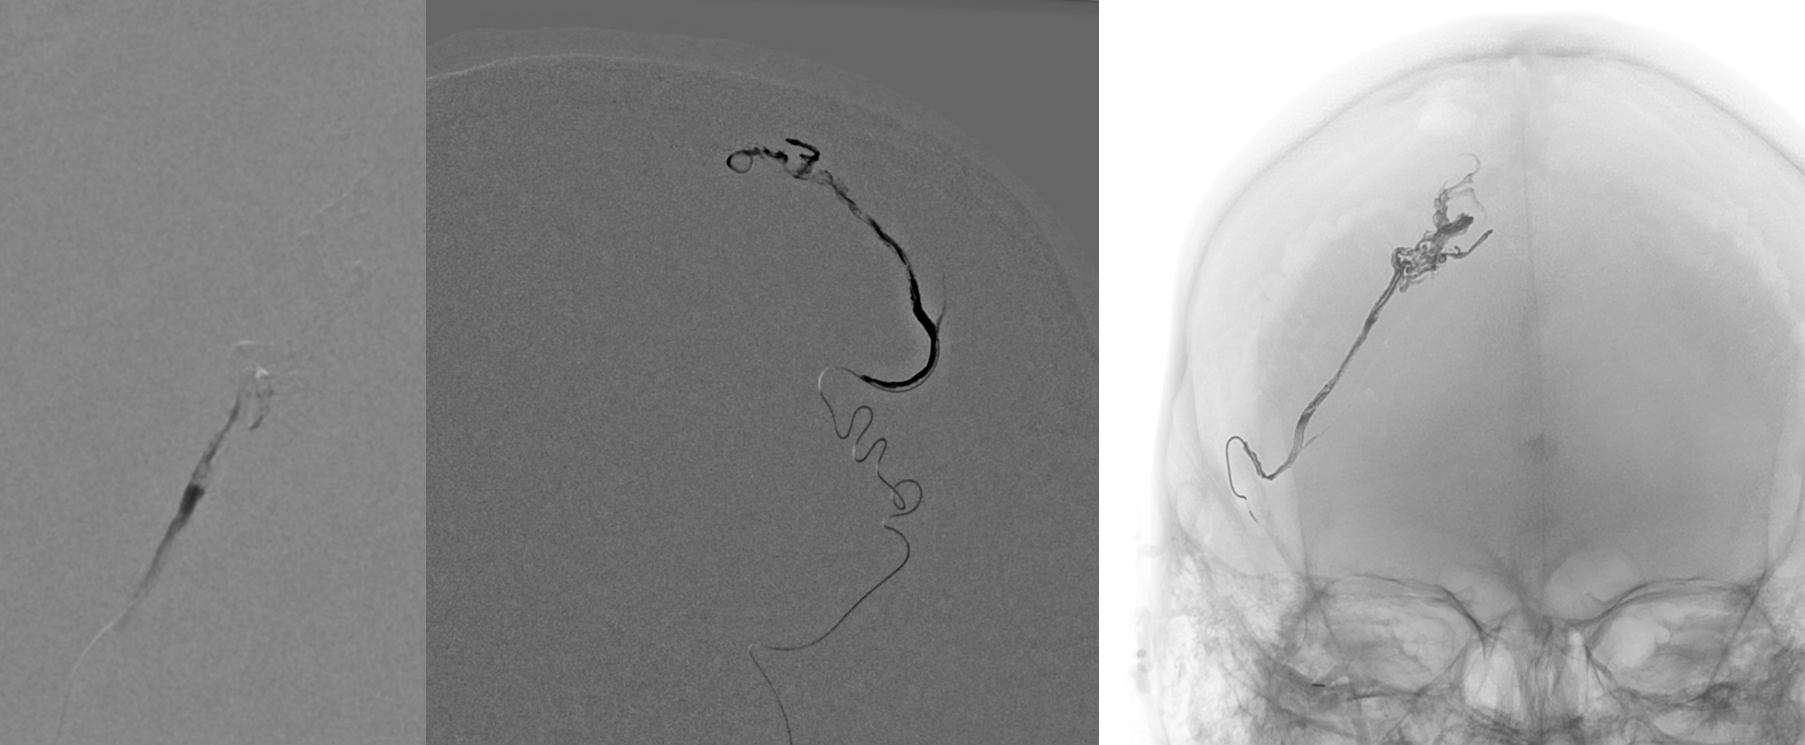

Reflux

Still alive. Why? Onyx is not adhesive etc etc? No…

How’s them apples. Reaccess is possible….

This shows the mistake. Can u see?